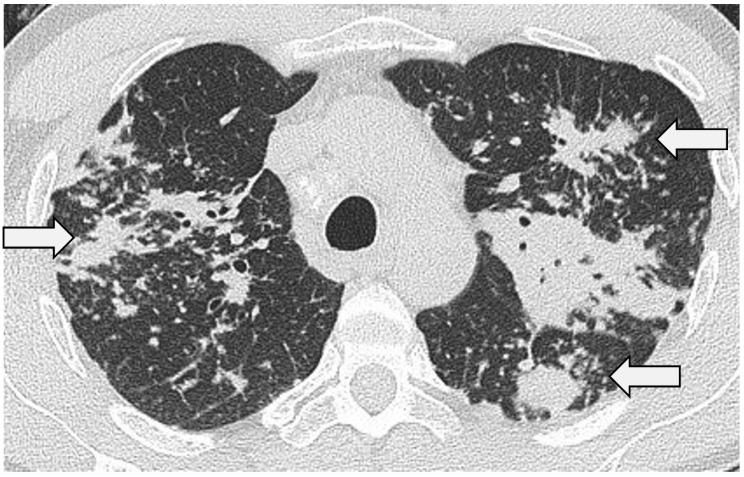

Sarcoidosis is the classic multisystem granulomatous disease. First reported as a disorder of the skin, it is now clear that, in the overwhelming majority of patients with sarcoidosis, the lungs will bear the brunt of the disease. This review explores some of the key concepts in the imaging of pulmonary sarcoidosis: the wide array of typical (and some of the less common) findings on high-resolution computed tomography (HRCT) are reviewed and, with this, the concept of morphologic/HRCT phenotypes is discussed. The pathophysiologic insights provided by HRCT through studies where morphologic abnormalities and pulmonary function tests are compared are evaluated. Finally, this review outlines the important contribution of HRCT to disease monitoring and prognostication.

结节病是典型的多系统肉芽肿性疾病。最初被报道为一种皮肤疾病,现在很清楚的是,在绝大多数结节病患者中,肺部会首当其冲受到疾病影响。本综述探讨了肺结节病影像学中的一些关键概念:回顾了高分辨率计算机断层扫描(HRCT)上一系列典型(以及一些不太常见)的表现,并据此讨论了形态学/HRCT表型的概念。评估了通过比较形态学异常和肺功能测试的研究,HRCT所提供的病理生理学见解。最后,本综述概述了HRCT对疾病监测和预后评估的重要贡献。